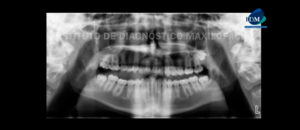

226 – Rizogénesis Incompleta

Paciente de 29 años acude al Instituto de Diagnóstico Maxilofacial para evaluación imagenológica de los incisivos centrales. A la evaluación de la radiografía panorámica se